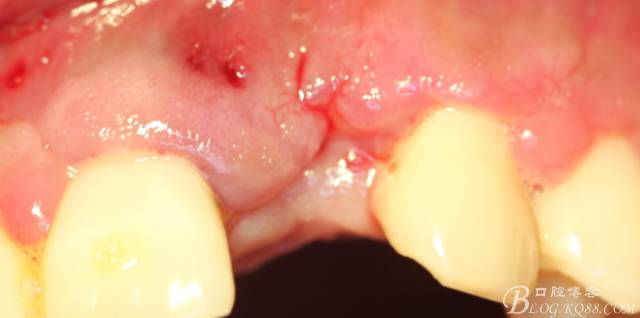

10天拆線一切正常,又過(guò)了兩周患者復(fù)診,自述期間無(wú)異常??趦?nèi)檢查,真的嚇了一跳,唇側(cè)鼓了個(gè)包,擠壓有白色分泌物溢出,絕對(duì)不是膿液,液體排除后,術(shù)區(qū)觸診空虛,外觀塌陷。這時(shí)候考研大夫的時(shí)刻到了,是先觀察一段時(shí)間再說(shuō)?還是馬上進(jìn)行處理?我的回答是:馬上處理!如果你沒(méi)有及時(shí)處理,而是放患者回家觀察,那么接下來(lái)會(huì)發(fā)生如下情況:1.回家后患者家屬及親友會(huì)有很多你可以想象得到的討論;2.患者及家屬會(huì)對(duì)你產(chǎn)生不信任,勢(shì)必會(huì)到其他門診或醫(yī)院檢查,他院大夫會(huì)不會(huì)發(fā)表對(duì)你不利的言論;3甚至?xí)蚁嚓P(guān)法律界人士找你討要說(shuō)法。